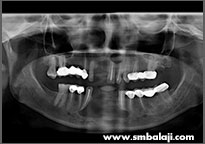

All impacted teeth removed